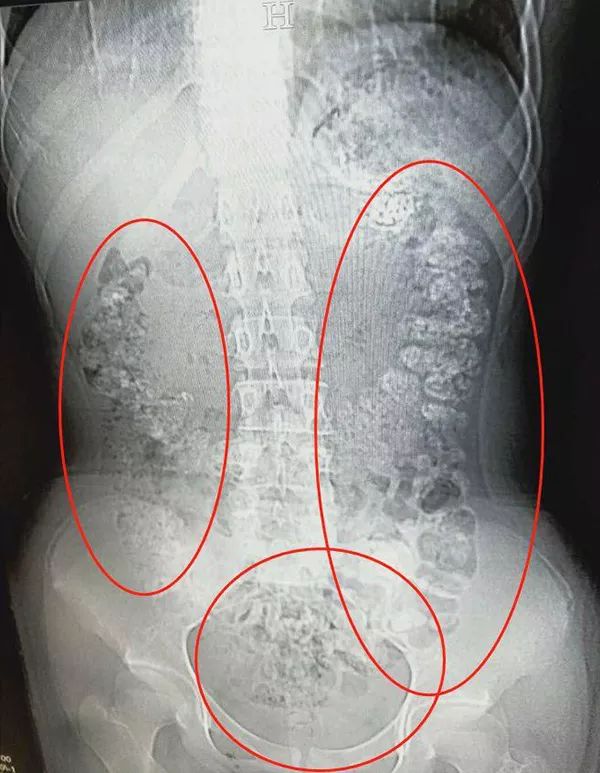

14岁女孩肚子疼,CT检查发现胃、肠、一直到…

600x773 - 70KB - JPEG